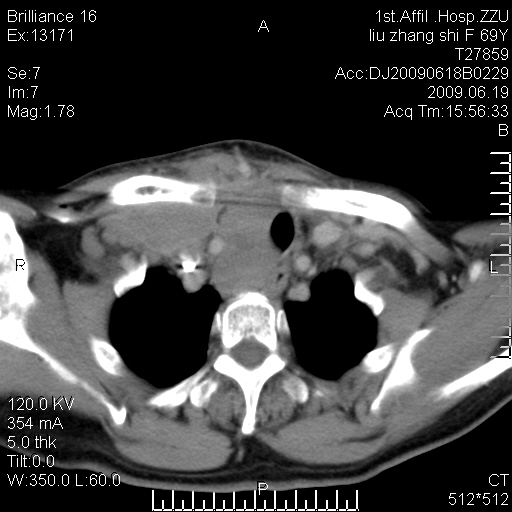

标题: CT26782:女,69岁,颈部占位,3天后公布病理结果。

【病理证实系列】女,69岁,颈部占位,有病理结果,3天后公布。(由于病例时间较久,临床资料不全,请网友见谅)本系列将有几百种常见、少见及罕见病例,均经病理证实。病例资料来自郑州大学第一附属医院。与网友共享,本人有空就发。

甲状腺癌并颈部淋巴结转移。感谢楼主的良苦用心,谢谢。

甲状腺癌并颈部淋巴结转移。

需与鼻咽癌鉴别!

支持甲状腺癌广泛侵及周围结构并颈部淋巴结转移。

鉴别:淋巴瘤、恶性神经源性病变、恶性纤维组织细胞瘤。

病理结果:颈部非霍奇金淋巴瘤。

右侧甲状腺确实有问题